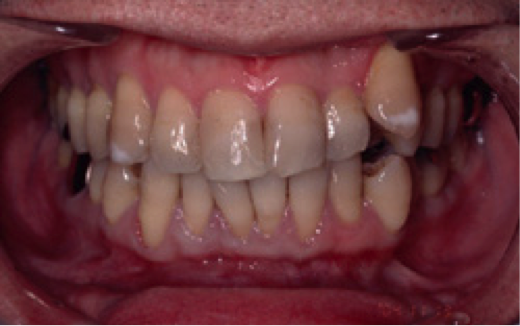

【男性(初診時38歳)非喫煙者】

歯肉が全体的に下がっていることを主訴に来院されました。特にひどいのが右下の犬歯付近で、ここについては手術を受けてでも治したいとのことでした。このような状態を歯肉退縮と呼びますが、原因は大きく分けて二つ考えられます。一つは強く歯を磨きすぎること、もう一つは歯ぎしりなどの噛み合わせの不具合です。必ず事前の診査により原因を除去しておかないと、手術をして元通りになったとしても、またすぐに下がってしまいます。この症例では口蓋より結合組織を採取し、右下犬歯の部分に移植しました。